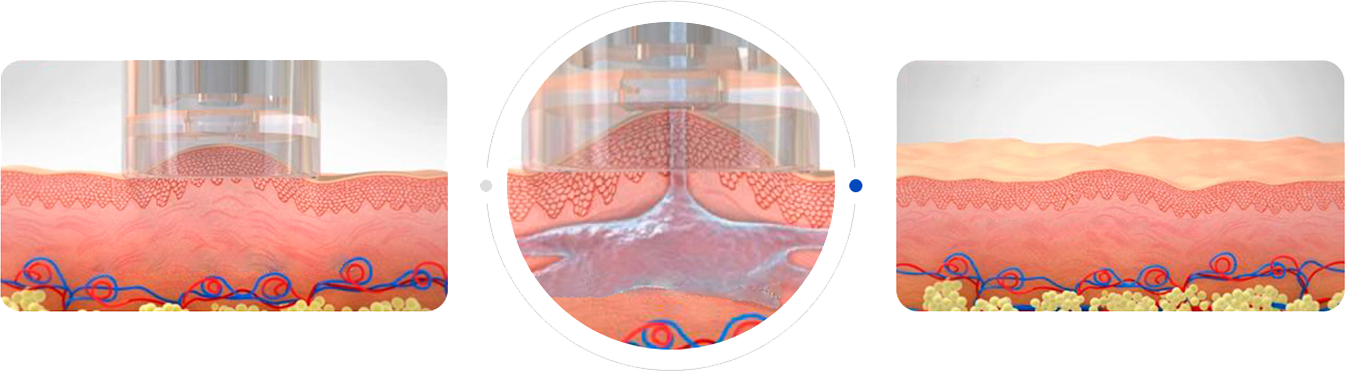

Transcutaneous Pneumatic InjectionSHEMAX uses compressed air pressure to spray liquid medicine instantaneously.

At this time, liquid medicine is delivered to a certain depth through physical energy.